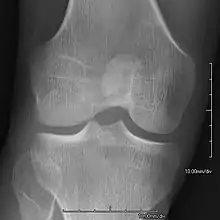

- Patellar involvement is present in approximately 90% of patients; however, patellar aplasia occurs in only 20%.

- In instances in which the patellae are smaller or luxated, the knees may be unstable.

An elbow of a man with nail–patella syndrome (NPS)